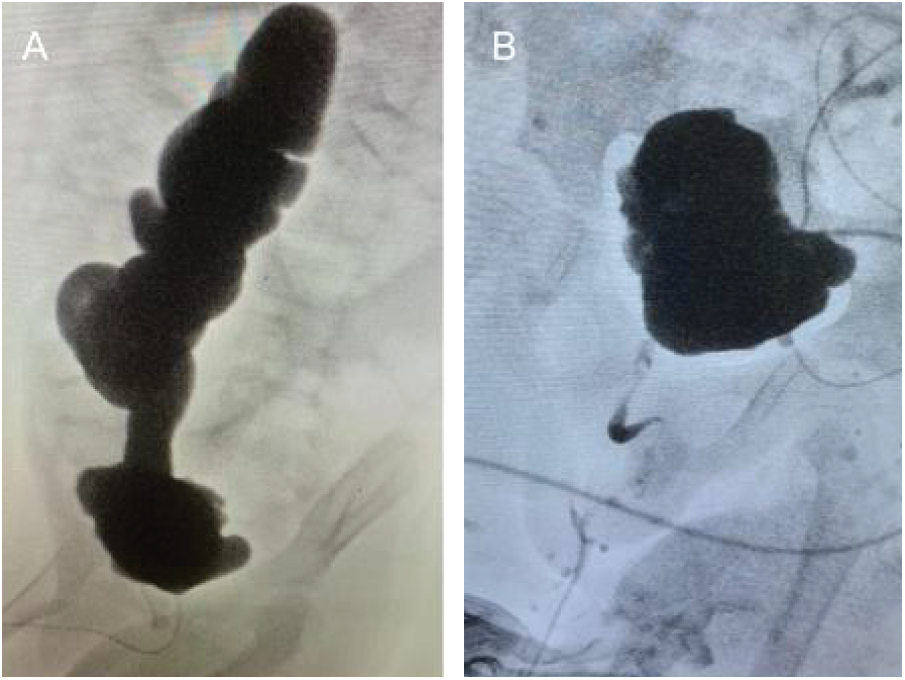

For our 5-year-old patient, expected bladder capacity was 210 mL. VCUG showed a bladder capacity of 50 mL and severe (grade V) right sided vesicoureteric reflux (VUR) (Figure 1A). His ultrasound indicated bilateral hydroureteronephrosis with parenchymal thinning. Due to low bladder capacity and VUR noted on diagnostic testing, right nephrectomy, ureterocystoplasty and Mitrofanoff procedure were performed.

FIGURE 1. A) preoperative cystogram showing small bladder and refluxing ureter that is severely dilated and tortuous. B) postoperative cystogram showing improved capacity and no reflux

Cystogram done one month postoperatively showed no leaks and a bladder capacity of 180 mL (Figure 1B). Post-operative creatinine came down to 141 umol/L and ultrasound showed significantly improved hydroureteronephrosis. Clean intermittent catheterization (CIC) was started every 4 h during the day and continuously overnight and he was started on an anticholinergic agent. He has done well for the past 4.5 years. Creatinine stabilized at 191 umol/L however in the last 6 months, it has started climbing to around 260 umol/L. VCUG shows 370 mL bladder capacity. This is aligned with expected bladder capacity of a 9-year-old of 330 mL as per the Koff formula.3 UDS were completed at the 3-year mark and shows no reflux and compliance of 11.4 mL/cmH2O. This child has avoided renal transplant thus far because of this procedure.